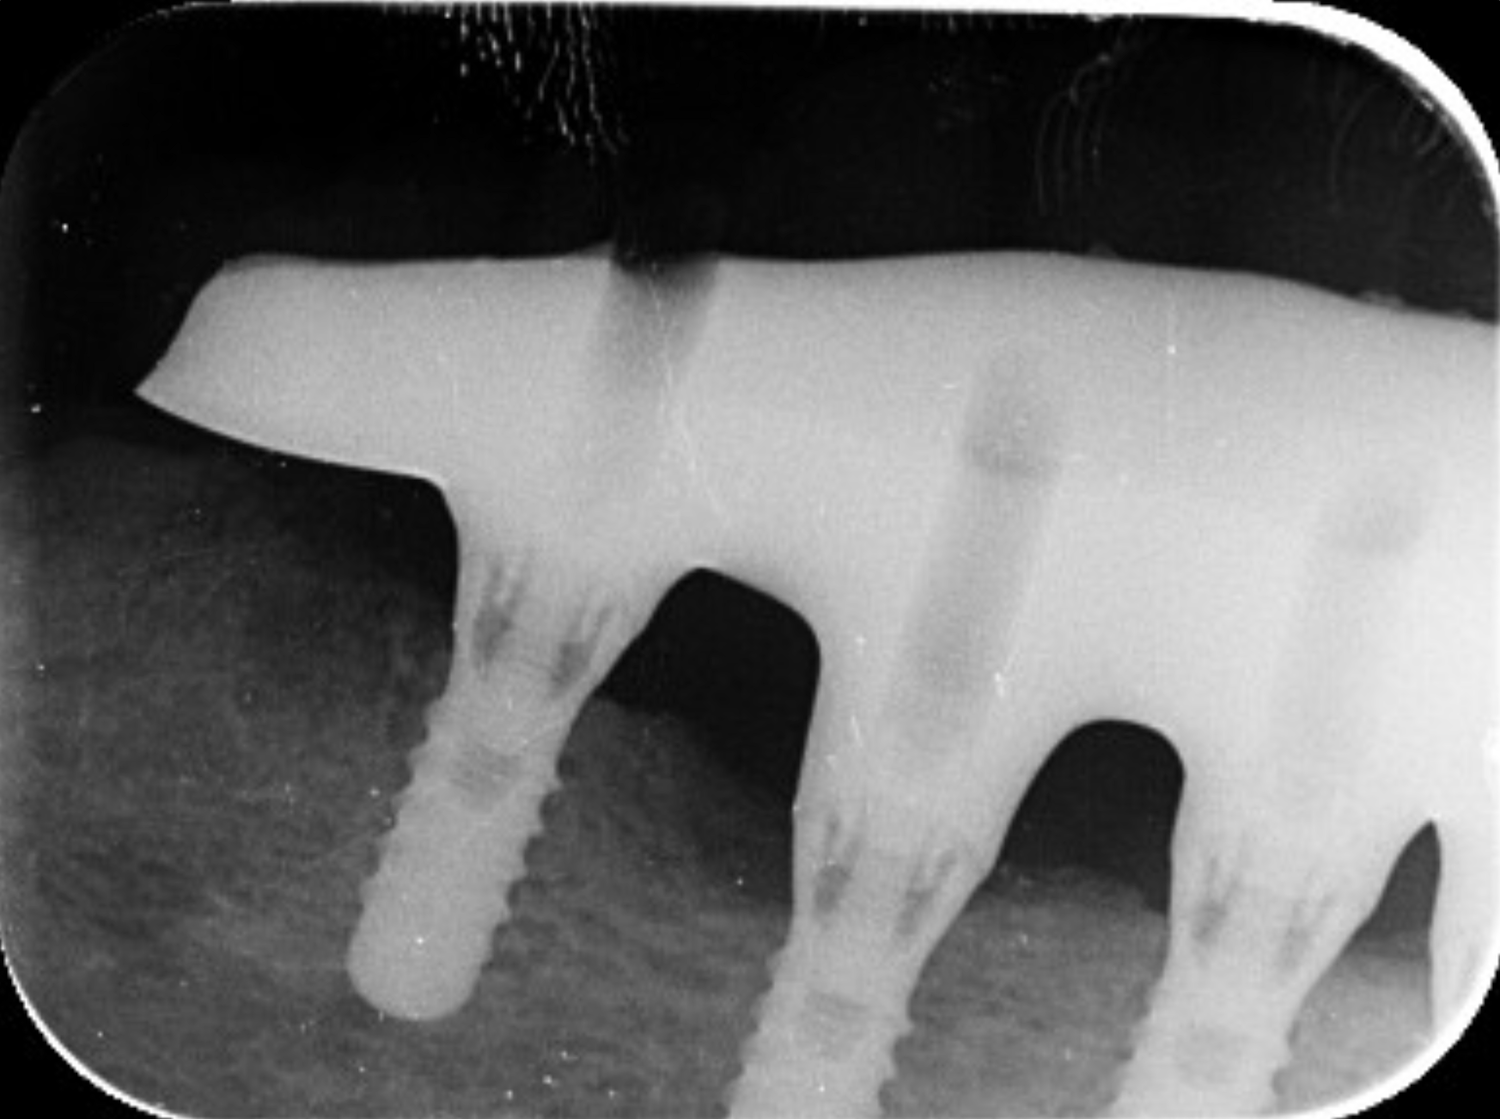

V posledních letech vidíme velký nárůst implantologických prací. Zhotovujeme náhrady na téměř 40 různých implantologických systémů, z nichž každý má několik variant podle typu, velikosti nebo řady implantátů. Každý implantát je jinak zavedený, a tak musíme vždy pečlivě rozhodnout, jaký cut použijeme podle toho jak hluboko je implantát zaveden.

Vnímáme také změnu preferencí lékařů – šroubované fixace jsou stále oblíbenější, ale někteří lékaři stále ještě dávají přednost cementovaným náhradám. Často také řešíme implantáty s odlišným sklonem, kde musíme rozhodnout, zda je nutné použít multiunit abutment.

Tohle všechno dělá práci s implantáty velmi komplexní. Není to jen o technice, ale hlavně o zkušenostech a schopnosti správně vyhodnotit každý případ.